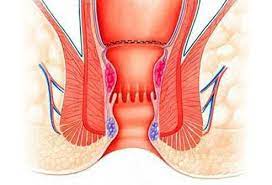

Overview

Package includes:

Days in hospital : 3 to 4 Days (For patient and one attendant)

Days in hotel : 10 Days (For patient and one attendant)

Room type in hospital : Shared

Room type in hotel : Private

Hotel category: Standard

Value added benefits of the Haemorrhoidectomy - Routine:

Ø Doctor consultation charges

Ø Lab tests and diagnostic charges

Ø Room charges inside hospital during the procedure

Ø Surgeon Fee

Ø Nursing charges

Ø Hospital surgery suite charges

Ø Anesthesia charges

Ø Routine medicines and routine consumables (bandages, dressings etc.)

Ø Food and Beverages inside hospital stay for patient and one attendant.

Extra benefits:

ü Interpreter

ü Visa assistance

Ø Site tourism of the city

Ø Follow up with the doctor

Ø Airport pick up and drop

Ø Free online consultation with the doctor

Ø Priority appointments with the doctor

Ø Room upgrade from sharing to private

Overview

Package includes:

Days in hospital : 2 to 3 Days (For patient and one attendant)

Days in hotel : 7 Days (For patient and one attendant)

Room type in hospital : Shared

Room type in hotel : Private

Hotel category: Standard

Value added benefits of the Stapler Haemorrhoidectomy:

Ø Doctor consultation charges

Ø Lab tests and diagnostic charges

Ø Room charges inside hospital during the procedure

Ø Surgeon Fee

Ø Nursing charges

Ø Hospital surgery suite charges

Ø Anesthesia charges

Ø Routine medicines and routine consumables (bandages, dressings etc.)

Ø Food and Beverages inside hospital stay for patient and one attendant.

Extra benefits:

ü Interpreter

ü Visa assistance

Ø Site tourism of the city

Ø Follow up with the doctor

Ø Airport pick up and drop

Ø Free online consultation with the doctor

Ø Priority appointments with the doctor

Ø Room upgrade from sharing to private